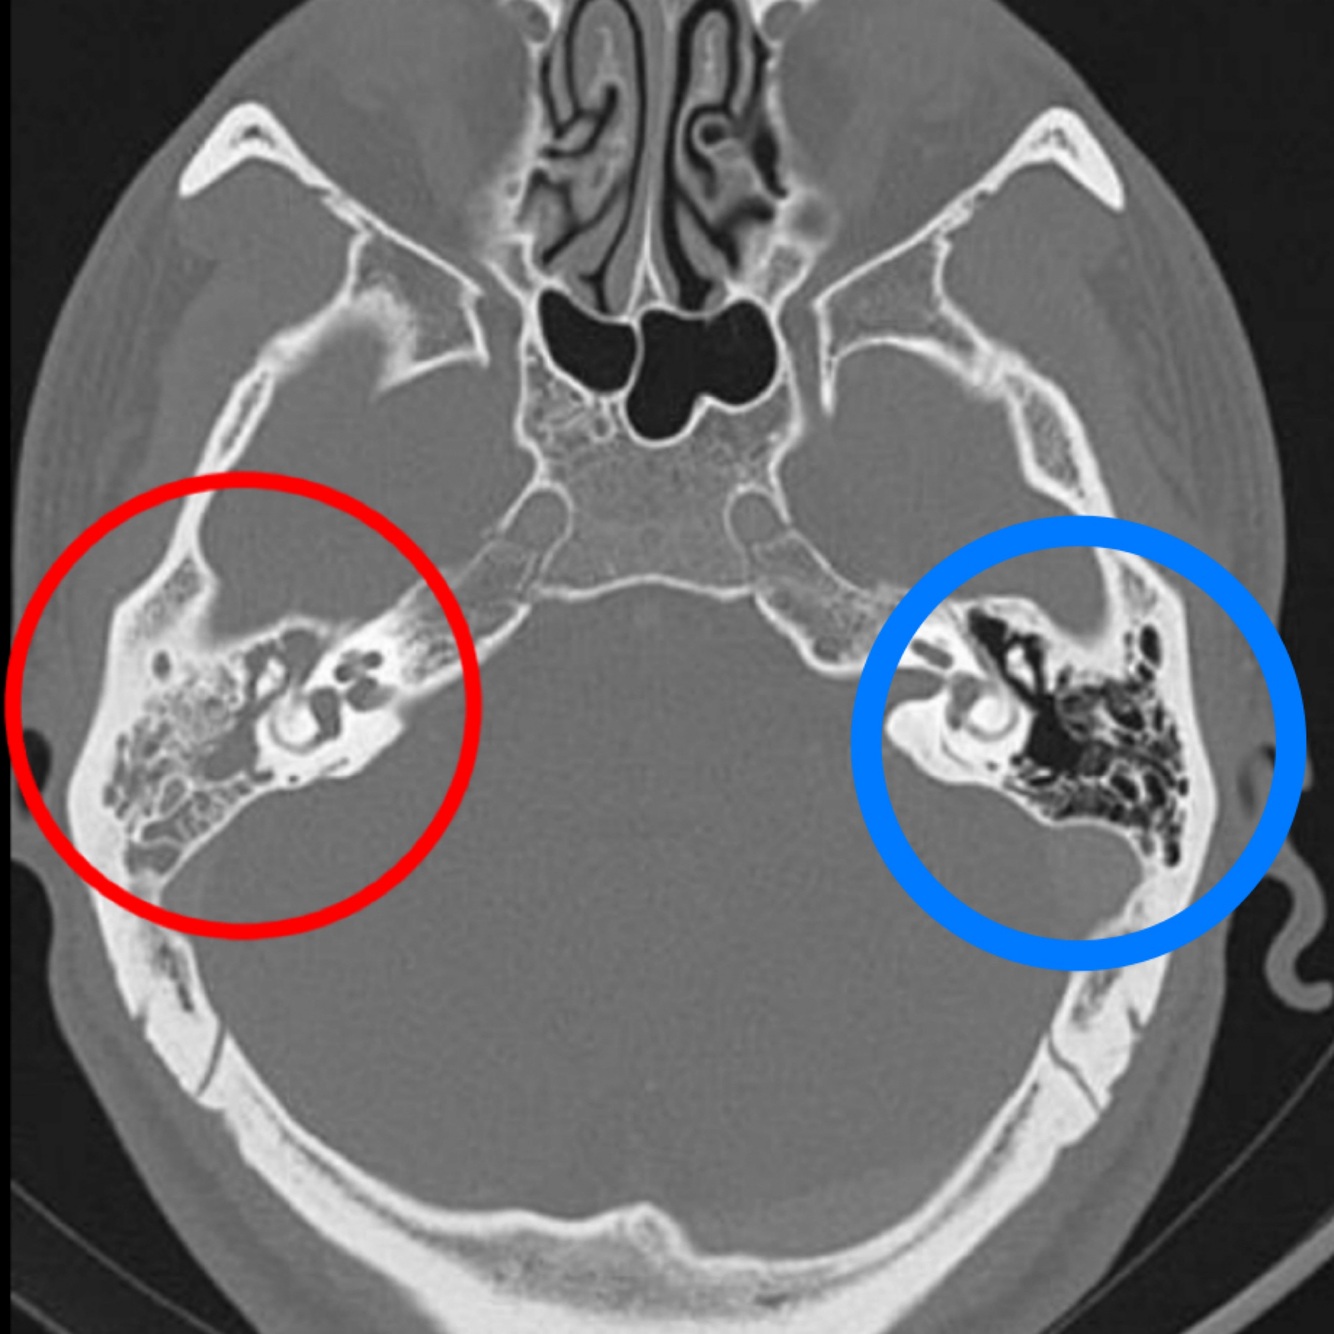

Hallazgos de TC:

• Opacificación de celdillas mastoideas

• Crónico: Esclerodiploico = engrosamiento óseo

Hallazgos en imagen:

RM o TC

• Otitis y mastoiditis

• Masa que destruye hueso

A (afectado): se pierden huesecillos

Estudio de imagen dx para colesteatoma:

DWI

Hiperintensa en T2